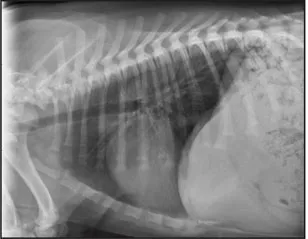

CASE 1.1 A 7-year-old neutered male Labrador Retriever who was hit by a car. You obtain these thoracic radiographs: Figs. 1.1a, b, left and right lateral projections, respectively; Figs. 1.1c, d, ventrodorsal and dorsoventral projections, respectively.

1.1b